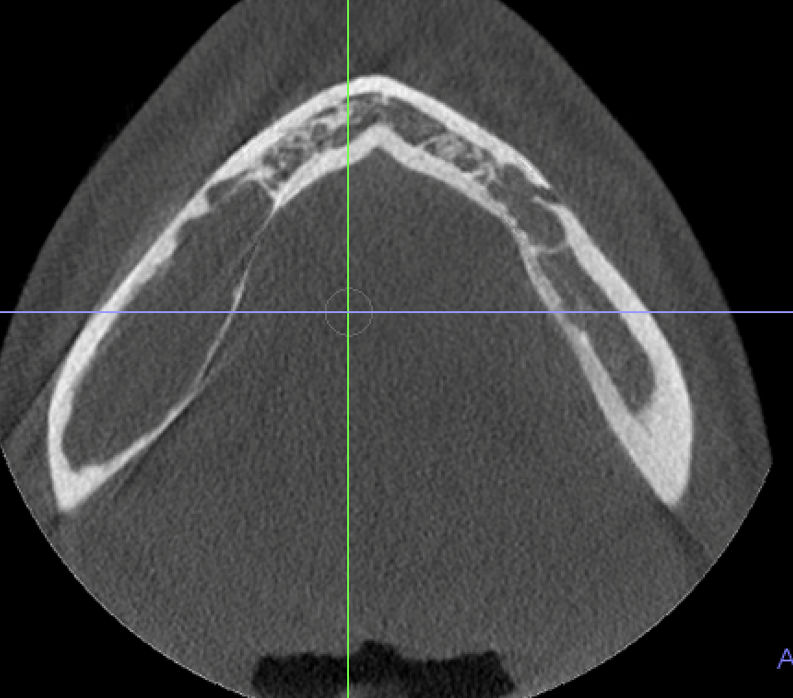

24-year-old woman with unusual radiolucency

A 24-year-old woman with an unusual radiolucency at the crown of tooth #14.